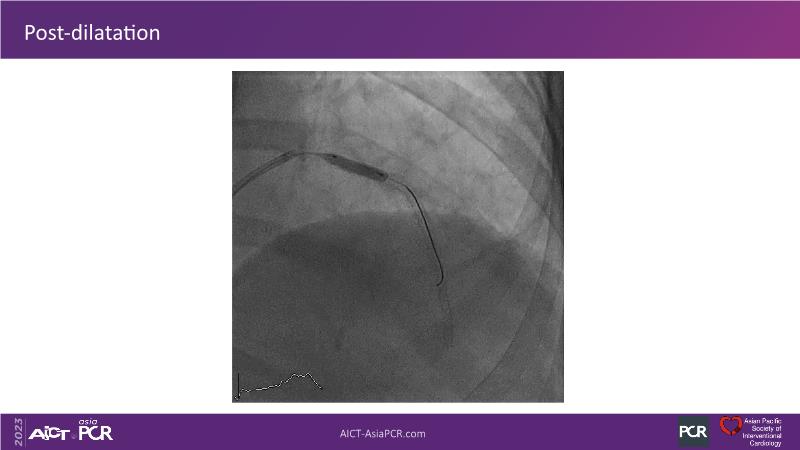

This session is recommended for you if you are seeking insights into the advantages of using IVUS imaging over visual assessment for better outcomes in left main bifurcation procedures. Discuss with experts the benefits of using RotaCUT in lesion preparation for left main bifurcation and explore the impact of high radial strength stents on the procedure's success.

• To know how a high radial strength stent can make a difference in left main bifurcation